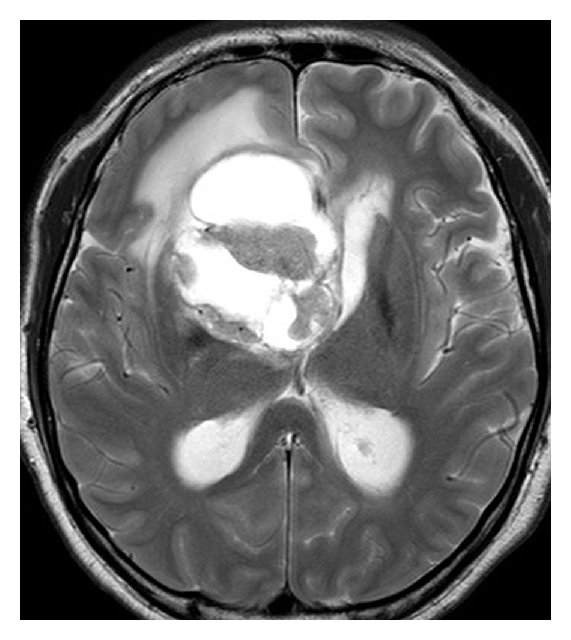

A 42-year-old Japanese man was admitted to our hospital for headache and nausea. These symptoms had progressed for 4 days before admission, and he was gradually unable to walk steadily. Magnetic resonance imaging (MRI) revealed a mass lesion with marked cyst components. The lesion had a maximum diameter of 58 mm (Figure 1). T1-weighted images (WIs) after gadolinium administration showed ring enhancement. T2WIs showed slight edema around the lesion. Proton magnetic resonance spectroscopy (1H-MRS) analysis of the nodule showed an increased ratio of choline to creatine and an apparent peak for lactate, which is strongly correlated with tumor malignancy. In contrast, the peak for N-acetylaspartate (NAA) was within the background noise level (Figure 2). The neuroimaging diagnosis was a primary malignant brain tumor such as glioblastoma multiforme (GBM) or a metastatic brain tumor. The patient underwent subtotal removal of the lesion via a fronto-temporal craniotomy.

(a)

(b)

(c)

(d)